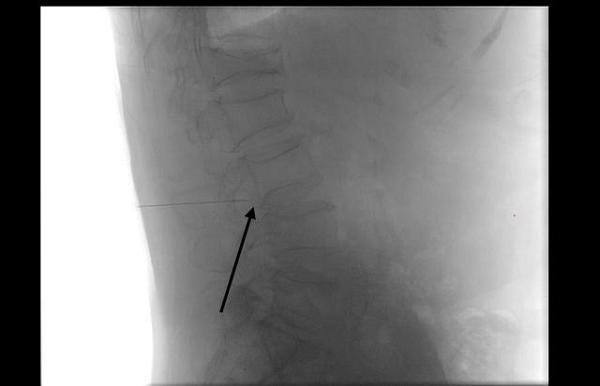

图:医生在影像引导下,精准定位病灶

图:细针穿刺至受压神经根,进行精准给药